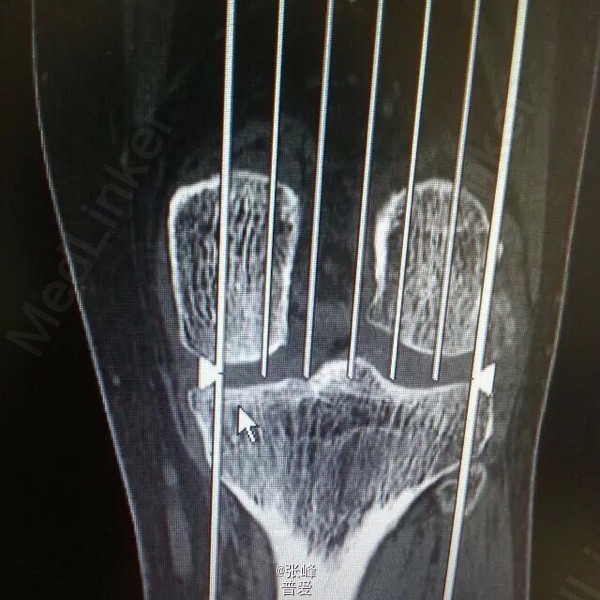

患者刘曙平,男,57岁。 左膝部肿痛、活动受限1天。 患者于昨天无明显诱因出现左膝肿胀,疼痛,伴活动受限。自行服药及局部外敷药治疗(具体不详),效果不明显,疼痛渐加重。为求进一步诊治,就诊我院,门诊了解病史、查体后以“左膝滑膜炎”收入院。 起病以来,精神一般,未进饮食,二便未解,体力尚好。 既往史:发现“高血压”4年,规律服用“倍他乐克”“波依定”,血压控制可;发现“痛风”20余年,目前症状控制一般。否认糖尿病、肝炎、结核等病史,否认药敏史。

体格检查:T:36.5℃ P:74bpm R:18bpm Bp:138/80mmHg。神志清晰,精神可。胸廓无压痛,双肺叩诊呈清音,听诊呼吸音清晰。心率74bpm,律齐,各瓣膜听诊区未闻及病理性心杂音。腹平,软,无压痛及反跳痛,肝脾肋下未触及,肠鸣音3-5次/分。 专科情况:左膝明显肿胀,膝眼饱满,局部皮温稍高,局部压痛,活动受限,背伸尚可,屈曲90度后受限,左足背动脉搏动良好,左足趾活动可。

诊断:左膝滑膜炎 诊疗计划:1.完善相关检查,如血尿常规分析、肝肾功能等。 2.对症治疗,观察左膝情况。 3.请示上级医师指导治疗。 者诉左膝部疼痛不适,无诉其他特殊不适,大小便正常。赵晶晶主治医师查房:患者根据既往病史、查体检查,目前考虑诊断左膝关节痛风性关节炎可能性大,暂以抗尿酸、对症支持及局部理疗,